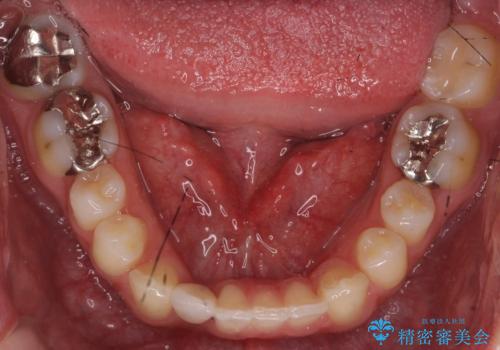

上はインビザラインで目立たないように前歯を下げ、下は難しいため、ワイヤー矯正で咬み込んでいる下の歯を沈める処置を初め行いました。最終的には上下ともインビザライン矯正で仕上げました。

下の前歯が生まれつき1本少なかったため、その部分には最終的にインプラントを入れ、下の歯が下がりすぎないようにかつ上の前歯にしっかり咬むように仕上げました。

今回は、時間はかかりましたが矯正治療で隙間を閉じ、天然の歯を保存することができました。セラミックで無理に一時的にかぶせるとその後大変な人生になるのが予想されます。

難ケースのため、患者様とともに根気強く治療に取り組んだ結果、しっかり治療することができました。